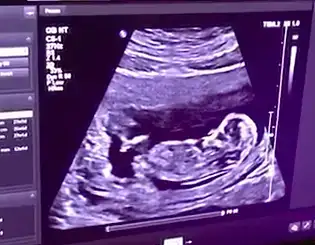

Bu da arkadaşımın bebişinin 12. haftasından görüntüsü. Yine tahmin rica edeceğiz sizden. Sevgiler

Eklentiler

• M 12 hafta.webp

M 12 hafta.webp

10,9 KB · Görüntüleme: 54